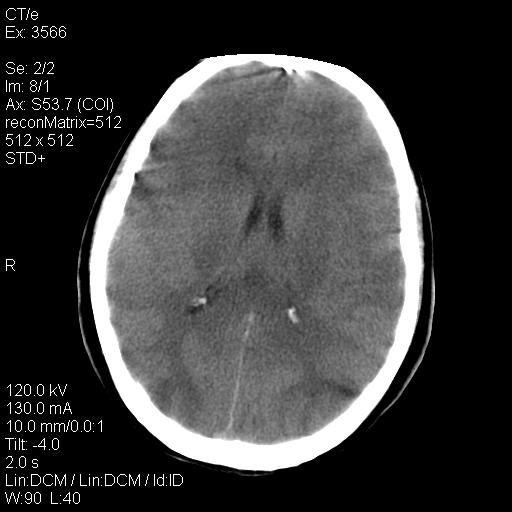

标题: CT9947:女,20岁,妊娠9个月,突然癫痫症状 [打印本页]

标题: CT9947:女,20岁,妊娠9个月,突然癫痫症状

双侧脑白质缺血缺氧性改变,并高度可疑“蛛网膜下腔出血”。

后可复性脑病,

考虑 妊娠子痫或妊高征

双侧脑白质缺血缺氧性改变.

考虑先兆子痫\\子痫致he,建议mri除外有无合并静脉窦血栓形成.

考虑pres

脑组织肿胀改变

的确应该考虑可逆性后部脑病综合症--pres。感谢天南地北老师的指引,又学了一招儿,开心,呵呵!

考虑可逆性后部脑病综合症

支持pres